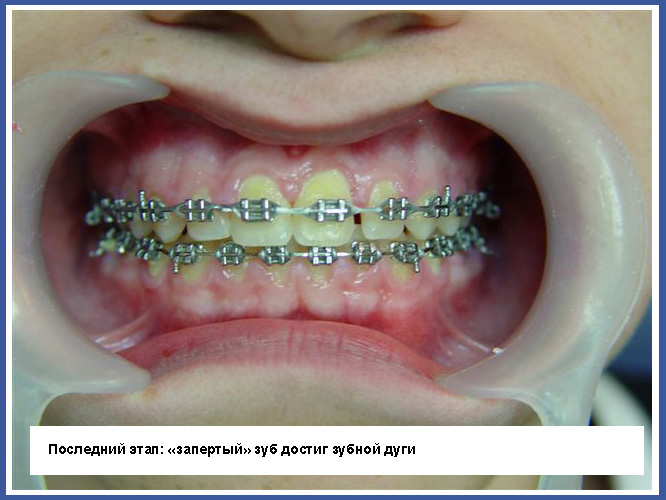

3.Если зуб «заперт» вследствие того, что траектория прорезывания неправильная, нужно обнажить «запертый» зуб хирургическим путем. Иногда простое обнажение зуба может изменить траекторию прорезывания, а иногда во время обнажения нужно приклеивать ортодонтическое приспособление на «запертый зуб» и активно вытягивать его на зубную дугу.

Шансы на удачное завершение лечения:

Лечение основывается на предположении, что «запертый» зуб не потерял свой потенциал прорезывания. Шансы достигнуть успеха в лечении «запертых» зубов очень велики в молодом возрасте (а в возрасте 40 лет составляют около 50%). Причина в том, что со временем зуб прирастает к кости в десне, а в таком случае теряется потенциал прорезывания зуба. Поэтому лучше прорезывать «запертые» зубы в более молодом возрасте.